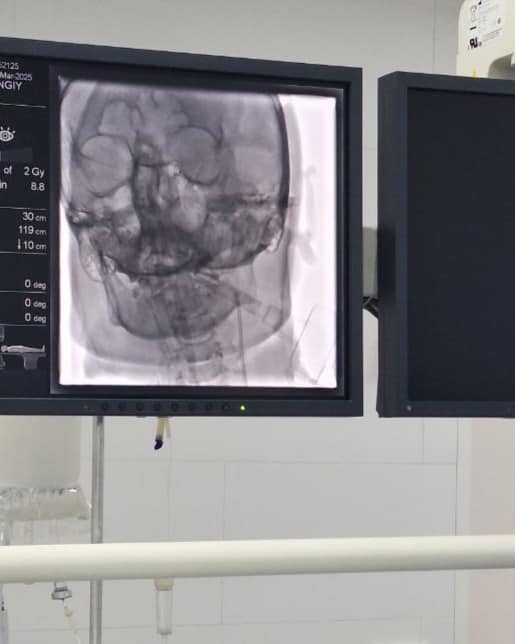

Вчергове у КНП «Нововолинська ЦМЛ» врятували пацієнта з інсультом. Хворому провели видалення тромбу з мозку мініінвазивно, через маленький прокол в паховій ділянці.

Тромбоекстракція – найсучасніший ендоваскулярний метод лікування ішемічного інсульту в гострому періоді. Він полягає у видаленні тромбу з артерій головного мозку з подальшим відновленням кровотоку та запобіганню розвитку ішемічного інсульту в даній ділянці.

Виконується дане ендоваскулярне втручання на ангіографічній системі за допомогою стента-ретрівера – спеціального циліндричного металічного пристрою, який вводиться безпосередньо в тромб, захоплює його і видаляє з закупореної судини.